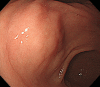

A 44-year-old woman presented to our hospital with abdominal pain. Abdominal ultrasonography and computed tomography showed a mass-like change in the lesser omentum between the liver and stomach. Esophagogastroduodenoscopy revealed a submucosal tumor-like change, and endoscopic ultrasonography (EUS) revealed that the mass was located outside of the stomach wall. We performed EUS fine-needle aspiration and diagnosed panniculitis of the lesser omentum. Based on these findings, we suggest that mass-like lesions in the lesser omentum and submucosal tumor-like changes in the anterior wall on the lesser curvature side of the stomach be evaluated for the possibility of panniculitis of the lesser omentum.